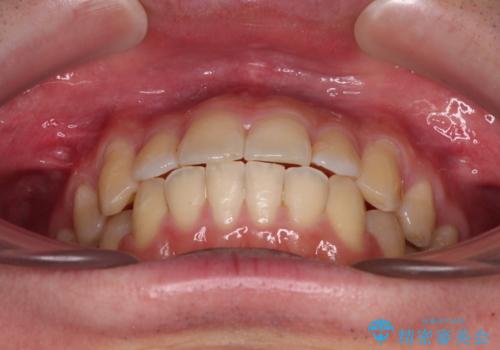

下顎前歯が思っていた以上に動きが悪く、想定よりも期間がかかってしまいました。

矯正治療後には気になっていた銀歯をセラミックで自然な色に仕上げました。